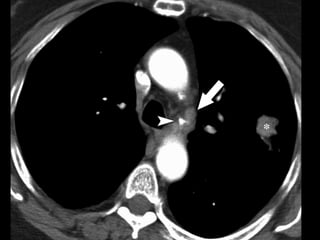

8. Paraesophageal LNs

• Upper border: carinal LNs.

• Lower border: diaphragm.

9. Pulmonary ligament LNs

• Pulmonary ligaments are inferior

extension of mediastinal pleural reflections

that surround the hila.

• Pulmonary ligaments LNs are located

posterior and inferior to the inferior

pulmonary veins.